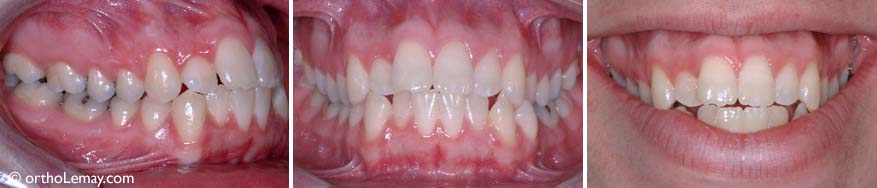

Sévère béance antérieure nécessitant de l’orthodontie et une chirurgie pour corriger la mauvaise relation entre les mâchoires d’un garçon de 17 ans.

Fermeture de la béance antérieure à la suite de l’orthodontie et d’une chirurgie aux mâchoires. Il en résulte une meilleure fonction (mastication et phonétique).